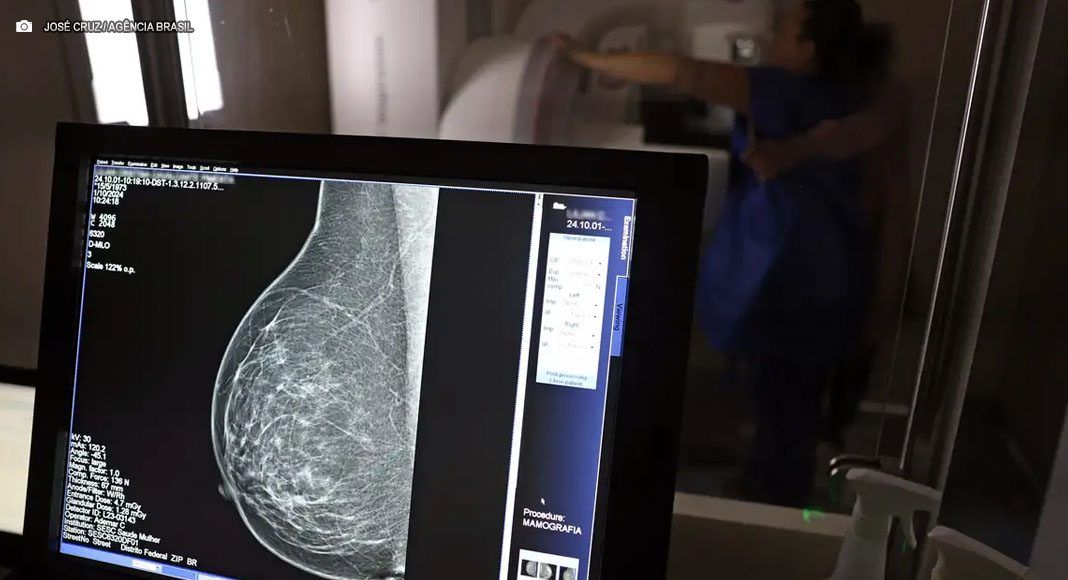

O Ministério da Saúde passou a recomendar o acesso à mamografia, via Sistema Único de Saúde (SUS), para mulheres na faixa de 40 a 49 anos, mesmo que não apresentem sinais ou sintomas de câncer de mama. Anunciada na última terça-feira (23/Set), a medida visa ampliar a detecção precoce da doença, que concentra 23% dos casos nessa faixa etária e tem maiores chances de cura com o diagnóstico antecipado. Até então, a orientação era que o exame fosse realizado apenas a partir dos 50 anos.

A recomendação para mulheres a partir dos 40 anos é que o exame seja feito sob demanda, em uma decisão conjunta com o profissional de saúde. Segundo nota do ministério, a paciente deve ser orientada sobre os benefícios e as desvantagens do rastreamento. “Mulheres nesta idade tinham dificuldade com o exame na rede pública de saúde por conta da avaliação de histórico familiar ou necessidade de já apresentar sintomas”, informou a pasta. Em 2024, as mamografias em pacientes com menos de 50 anos já representam 30% do total no SUS, somando mais de 1 milhão de exames.

Outra medida anunciada foi a ampliação da faixa etária para o rastreamento ativo, no qual a mamografia é solicitada preventivamente a cada dois anos. A idade limite, que era de 69 anos, agora passa a ser de 74 anos. Dados do ministério apontam que quase 60% dos casos de câncer de mama estão concentrados entre 50 e 74 anos. A pasta reforçou que a mudança aproxima o Brasil de práticas internacionais e fortalece o compromisso com o diagnóstico precoce, lembrando que o câncer de mama é o que mais mata mulheres no país.